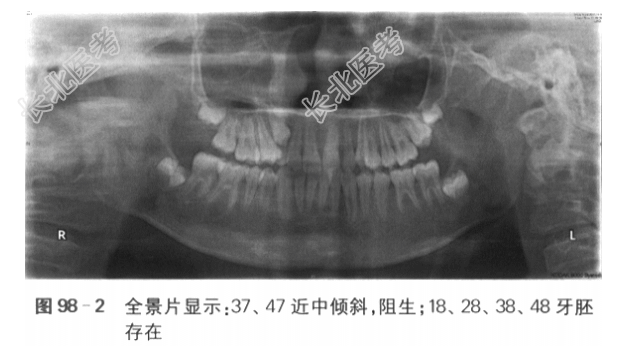

[材料题] 一、病历资料:1.主诉前牙“地包天”3年,牙齿不齐,要求矫治。2.现病史患者男性,10岁,前牙反咬,“地包天”3年余,自觉牙齿不齐,影响美观,要求矫治。否认吐舌、吮指、咬上唇等不良习惯史,否认口呼吸史。3.既往史患者乳牙合期有“地包天”史,未进行相关治疗。否认外伤史,否认家族史。否认系统疾病史。4.临床检查(1)正面观:面部基本对称,下颌无偏斜。(2)侧面观:凹面型,下唇外翻。(3)颞下颌关节检查:张口度、张口型正常,双侧颞下颌关节未及弹响,无压痛。口内检查:混合牙列,上颌654c21~12c456,下颌76E4321~67,6近中关系,16、12、11、21、22、26反,反覆盖浅,反覆深,下中线左偏2mm,上牙弓狭窄,上前牙直立,重度拥挤,15腭侧错位,14、24颊侧错位,下颌3~3重度拥挤,22过小牙,口腔卫生良好,牙周健康。下颌可后退至切对切(见图98-1)。5.影像学检查6.模型分析(1)上牙弓拥挤度:未测量(13、23阻萌,15腭侧错位,重度拥挤)。(2)下牙弓拥挤度:4mm。(3)下颌Spee曲度:4mm。(4)前牙Bolton比:80.3%。(5)全牙Bolton比:92.7%。二、诊断与诊断依据:(1)骨性Ⅲ类,上颌轻度发育不足,下颌轻度发育过度:头颅定位侧位片测量值显示SNA78°,SNB80°,ANB-2°,Ao-Bo-8mm,APDI95°。(2)安氏Ⅲ类:前牙反,第1恒磨牙近中关系。(3)牙列拥挤:全景片显示上颌双侧尖牙阻萌,模型测量显示下颌拥挤度为4mm,上颌15腭侧错位。(4)13、23阻生可能。